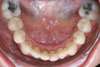

Encombrements traités par gouttières

E-Intermédiaire 1